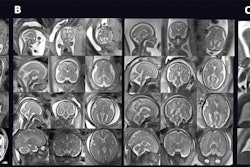

Ruiz and colleagues wanted to evaluate the type and frequency of maternal findings incidentally identified during fetal MRI. They looked at data from 455 consecutive fetal MRI exams from 429 women with an average age of 30 years, performed between 2017 and 2021.

Two fellowship-trained radiologists reviewed the exams independently to determine the type and frequency of incidental maternal findings. Differences in acquisition were resolved by two-reader consensus.

The researchers found that at least one incidental maternal finding was identified in 58% of the exams (n = 265). The most common findings included umbilical hernias (35%), maternal hydronephrosis (19%), and maternal hydro-ureter (15%). In total, 70% of all incidental maternal findings were related to pregnancy status.

The team also reported that two exams (0.5%) showed clinically significant incidental maternal findings, including pancreatic pseudocyst and ovarian cyst.